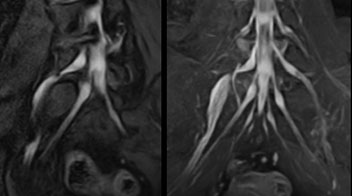

Distinguishing typical from atypical herniation informs the surgeon

“Although symptoms of typical disc herniation and atypical hernia are very similar, the actual site of herniation is different. It is therefore important to characterize the nerve’s condition both inside and outside of the intervertebral foramina. “Conversely, if we see no abnormality in NerveVIEW, we can assume at least that there is no severe condition that requires surgery. Like this, it can help us avoid unnecessary surgery. NerveVIEW can have a tremendous impact in this way.”

“NerveVIEW is really useful for those cases where a nerve disorder is strongly suspected based on the clinical examination but our regular MRI images do not show any findings. These atypical herniations and spinal canal stenosis, occurring in 5% to 15% of the total lumbar herniation/stenosis cases are our main target when using NerveVIEW,” says Dr. Yabuki.

"Because NerveVIEW helps us identify the actual hernia site, it can inform selection of the surgical approach"

“Recently, the two surgical methods extreme and oblique lateral interbody fusion (XLIF and OLIF) have become mainstream for minimally invasive treatment of lumbar spinal canal stenosis and intervertebral foramen stenosis. With these surgical techniques, the spine is approached from the flank, and prior knowledge of the exact anatomy of the lumbosacral plexus would be extremely helpful. To that end, high slice resolution (less than 1 mm acquisition) that enables sharper sagittal MPR images will be needed.”

Building confidence with NerveVIEW

“NerveVIEW can clearly show nerve courses and presence of nerve compression. However, when multiple abnormalities are seen, it can still be hard to determine which nerve is causing the symptoms,” says Dr. Yabuki. “In our experience so far, we see abnormal findings on NerveVIEW in about 70% of elderly patients. As the pain is usually caused by only one nerve, we thus need to find the exact corresponding nerve.” “With a nerve root block, the patient's pain is improved by infiltration of local anesthesia directly around the nerve root considered to be responsible. Knowing such nerve root block findings prior to image interpretation, helps to easily recognize abnormal findings on NerveVIEW as well. In other words, without a priori knowledge, based on symptoms and/or nerve root block findings, we must be aware of the possibility of overdiagnosis.”